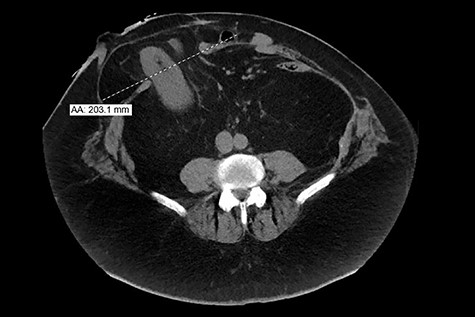

Laboratory values showed evidence of an acute kidney injury with suggestive urinary tract infection. Renal ultrasound demonstrated bilateral nephrolithiasis with moderate left hydronephrosis. Abdominal/pelvic CT scan confirmed left proximal ureteral stone with left hydronephrosis and a prominent parastomal hernia at the ileostomy site, which contained portions of the right kidney, right proximal ureter, mesenteric/retroperitoneal fat and some bowel (Fig. 2).

CT image from 2019 shows a prominent (2.3 cm ML) ventral hernia at the ostomy site, including portions of mesenteric/retroperitoneal fat, portion of right kidney, right proximal ureter and some bowel.